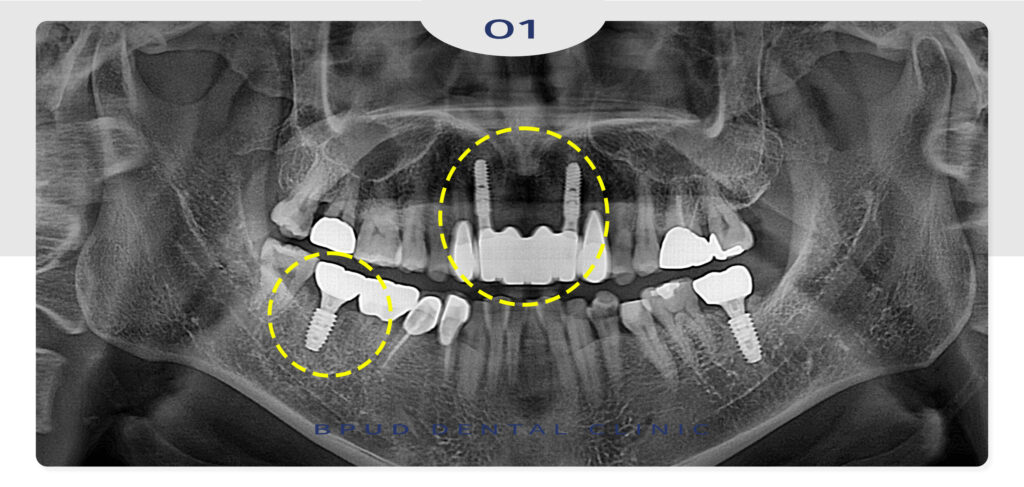

우선 가장 앞쪽에 보이는 앞니 네개를

발치하고 임플란트 2개를 식립하였으며

양쪽의 송곳니는 크라운 수복을 진행하기로 하였는데요.

인공치근과 잇몸뼈가 단단히 융합될 수 있는

기간을 기다려주는 동안 통증으로 인해

상태가 좋지 않았던 오른쪽 아래 어금니도

발치 후 임플란트 식립을 진행하였습니다.